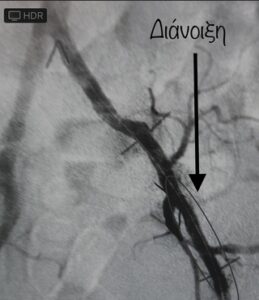

Ολική απόφραξη έξω λαγονίου αρτηρίας , επιτυχής διάνοιξη με ελάχιστα επεμβατική μέθοδο (αγγειοπλαστική)